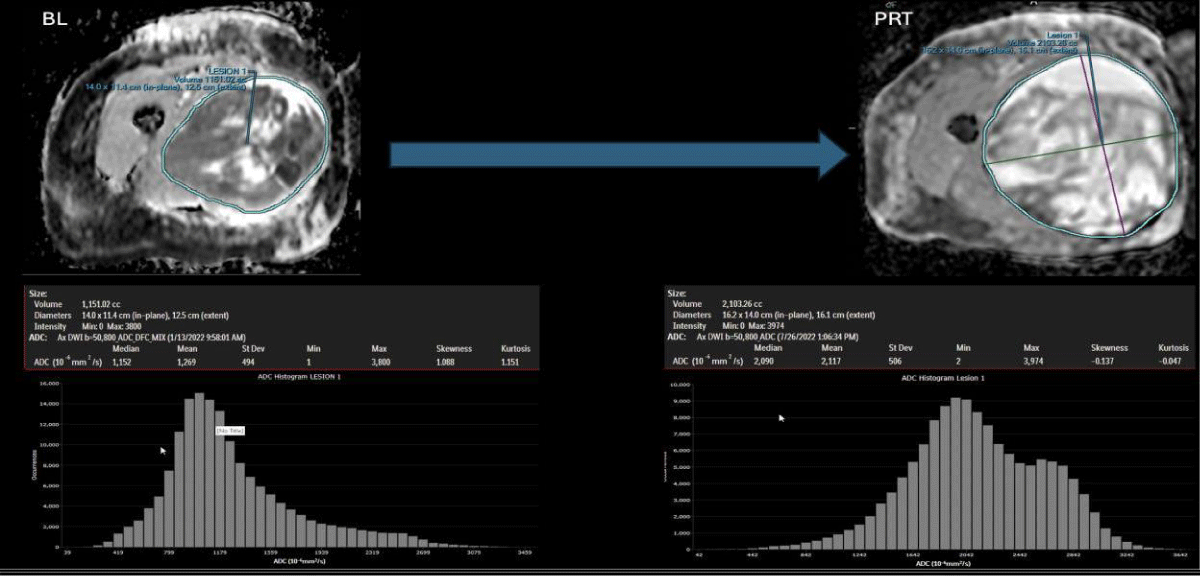

DWI is a non-invasive functional MRI sequence sensitive to the density of tumor cells within STS. By probing the random movement of water molecules, DWI is able to characterize the cellularity of malignant tumors, which generally have fewer extracellular spaces and smaller cytoplasm than benign tissues [13,19,20. To quantify the degree of diffusion, the Apparent Diffusion Coefficient (ADC) values can be computed using either a simple mono-exponential model or more sophisticated models [20,21]. The restricted diffusion in malignancies generally results in lower ADC values, which can help distinguish them from benign lesions, which typically demonstrate higher ADC values [5]. Effective therapy resulting in cell death increases water diffusion and higher ADC values. ADC values are inversely correlated with the Ki67 labeling index (a tumor cell division rate measure, typically considered high above 30), displaying a low mean in high proliferation groups [12,22]. DWI/ADC has demonstrated value as a potential biomarker of response in sarcoma patients treated with preoperative radiation therapy [5,23,24]. Patients with successful responses to treatment (> = 90% PATE) typically present a post-therapeutic right-sided ADC histogram with negative skewness (Figures 1,2) and higher ADC mean than poor responders [5,25]. Tumor changes at the cellular level occur before morphologic changes, making DWI/ADC a potential prognostic tool if performed early in treatment [24-27].

Figure 1: Case of pseudo-progression in a good-responder case: At the left panels, BL: Baseline/pre-treatment UPS ADC map, displaying central necrosis, a peripheral solid restricting tumor, and a left-sided intensity histogram. At the right panels and after completing 6 months of systemic therapy and radiation therapy (PRT: Post-Radiation Therapy), the tumor demonstrates a significant increase in volume (pseudo-progression), reduction in the solid diffusion restricting tumor, increase in mean ADC (from 1.2 to 2.1 x 10-3/mm2, reduction in skewness (from 1.0 to - 0.14) and an overall right-sided displaced histogram.